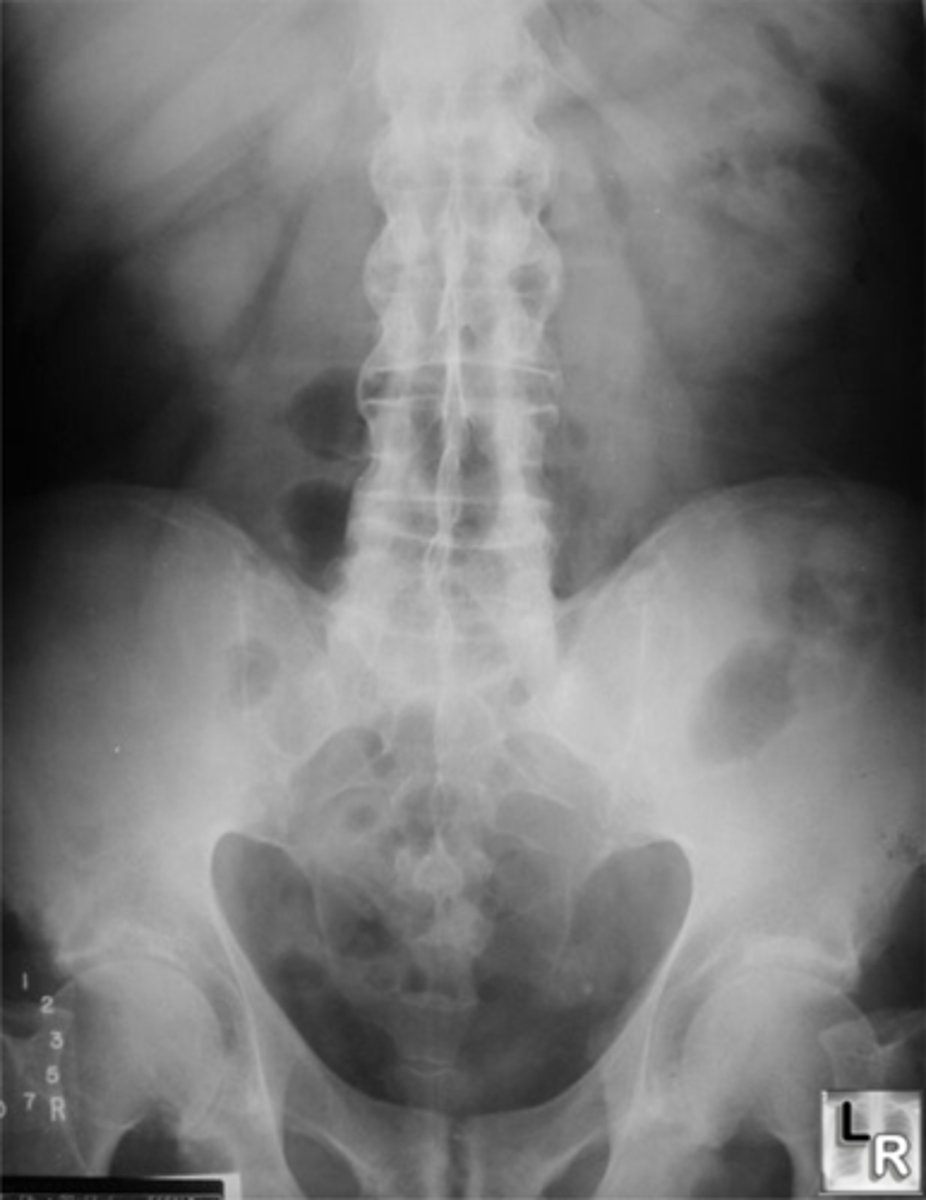

Vignette # 27

Sex: Male

Age: 52

Chief Complaint: Patient presents with mid to low back pain. Pain is felt in every direction

Objective Findings: Kemps -, Yeoman’s + in hip ,thorarcolumbar junction and lumbar spine, coxa vara bilaterally

Diagnostic Imaging: X-ray

1. What are the differential diagnoses? (Choose 3)

a. Paget’s (<50)

b. Fibrous dysplasia

c. Berkett’s lymphoma

d. Multiple myeloma

e. Blastic Metastasis (>40, no cortical thickening)

f. Hodgkin’s (20-40)

g. Lytic Metastasis

h. Hyperparathyroidism

Skull

Femur

Pelvis

a. Skull

b. Colon

c. Ulna

d. Liver

e. Lung (if hodgkins)

f. Femur

g. Pelvis

h. Heart

Malignant degeneration

Spinal canal stenosis

Tibial deformity

3. What’s the possible sequelae of this condition? (Choose 3)

a. Malignant degeneration

b. Spinal canal stenosis

c. Horner’s

d. Dyspnea

e. Tibial deformity (Saber shin)

f. Lymph node obstruction

g. Pathological collapse (bbt)

h. Lystic destruction